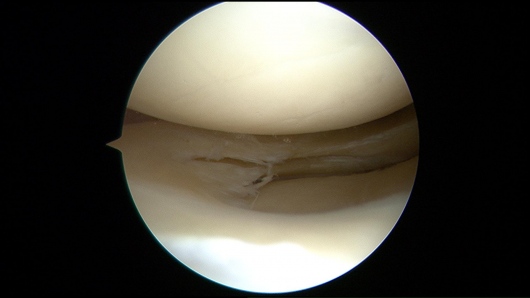

Además de la cirugía de reemplazo articular, me especializo en procedimientos de preservación articular y artroscopia de cadera y rodilla, buscando siempre retrasar o evitar la cirugía de reemplazo articular cuando es posible.

- Artroscopia

- Desgarre de meniscos